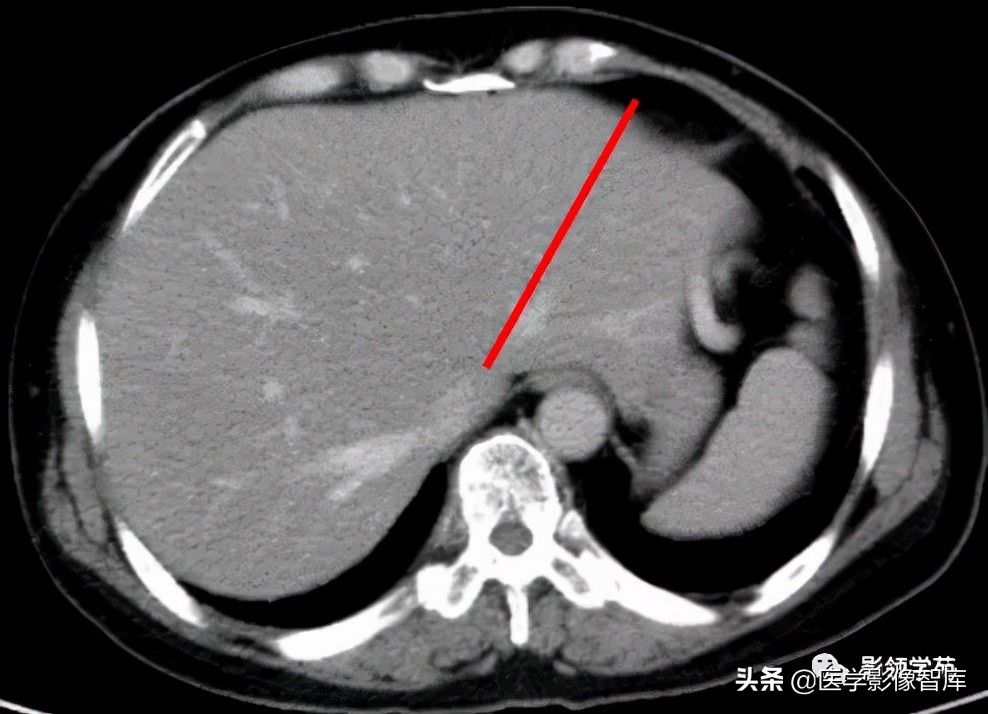

3、左段间裂:又称左门裂,相当于肝左静脉的长轴,将左外叶为外上段与外下段。

4、右叶间裂:在肝门以上的断层中相当于下腔静脉右缘与肝右静脉长轴的连线。在肝门以下为肝门横沟后缘或肝门静脉右支,与肝右静脉或右前、后支之间的连线;将右半肝为前方的右前叶和后方的右后叶。肝裂有肝右静脉走行。

胆囊窝层面CT横断面解剖